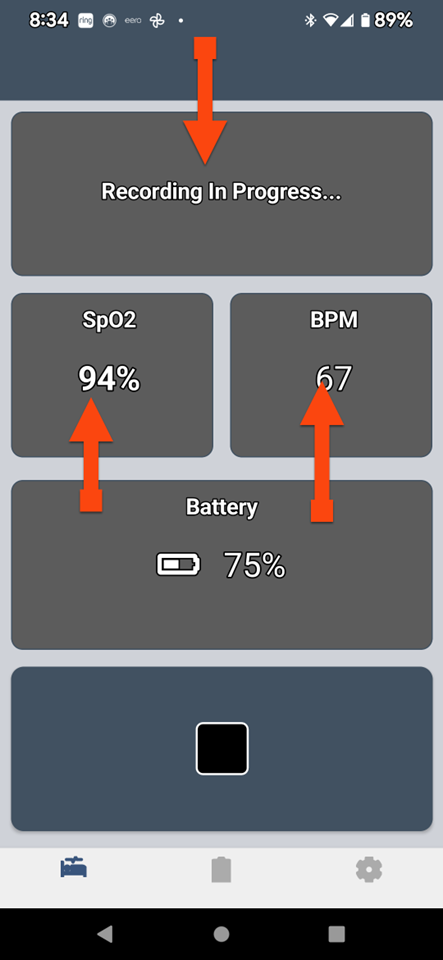

SLEEPIMAGE APP (Android)

SLEEPIMAGE APP (Android)

SLEEPIMAGE APP (Android)

SLEEPIMAGE APP (Android)

SLEEPIMAGE APP (Android)

SLEEPIMAGE APP (Android)

SLEEPIMAGE APP (Android)

SLEEPIMAGE APP (Android)

SLEEPIMAGE APP (Android)

SLEEPIMAGE APP (Android)

SLEEPIMAGE APP (Android)

SLEEPIMAGE APP (Android)

SLEEPIMAGE APP (Android)

SLEEPIMAGE APP (Android)

SLEEPIMAGE APP (Android)

SLEEPIMAGE APP (Android)

SLEEPIMAGE APP (Android)

SLEEPIMAGE APP (Android)

SLEEPIMAGE APP (Android)

SLEEPIMAGE APP (Android)

SLEEPIMAGE APP (iPhone)

SLEEPIMAGE APP (Android)

SLEEPIMAGE APP (Android)

SLEEPIMAGE APP (Android)

SLEEPIMAGE APP (Android)

SLEEPIMAGE APP (Android)

SLEEPIMAGE APP (Android)

SLEEPIMAGE APP (Android)

SLEEPIMAGE APP (Android)